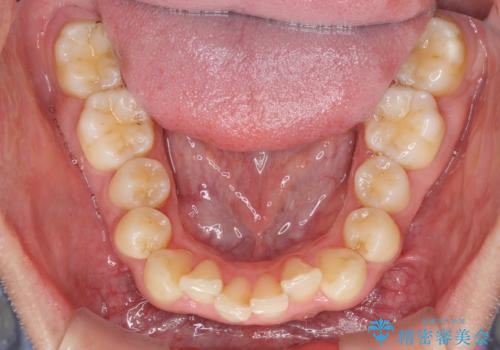

前歯のデコボコをスッキリ改善 インビザライン矯正

- 上下前歯のデコボコを気にして来院された患者様です。

全体的に叢生は軽度であったため、インビザラインにて矯正治療を行うこととしました。

デコボコの改善はもちろん、下顎前歯が隠れてしまうディープバイトも一緒に改善することができ、奥歯への負担を軽減することができました。